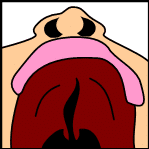

Tonsillitis

Cheatsheets

2

Mnemonics

0

Images

1

Picmonic

0